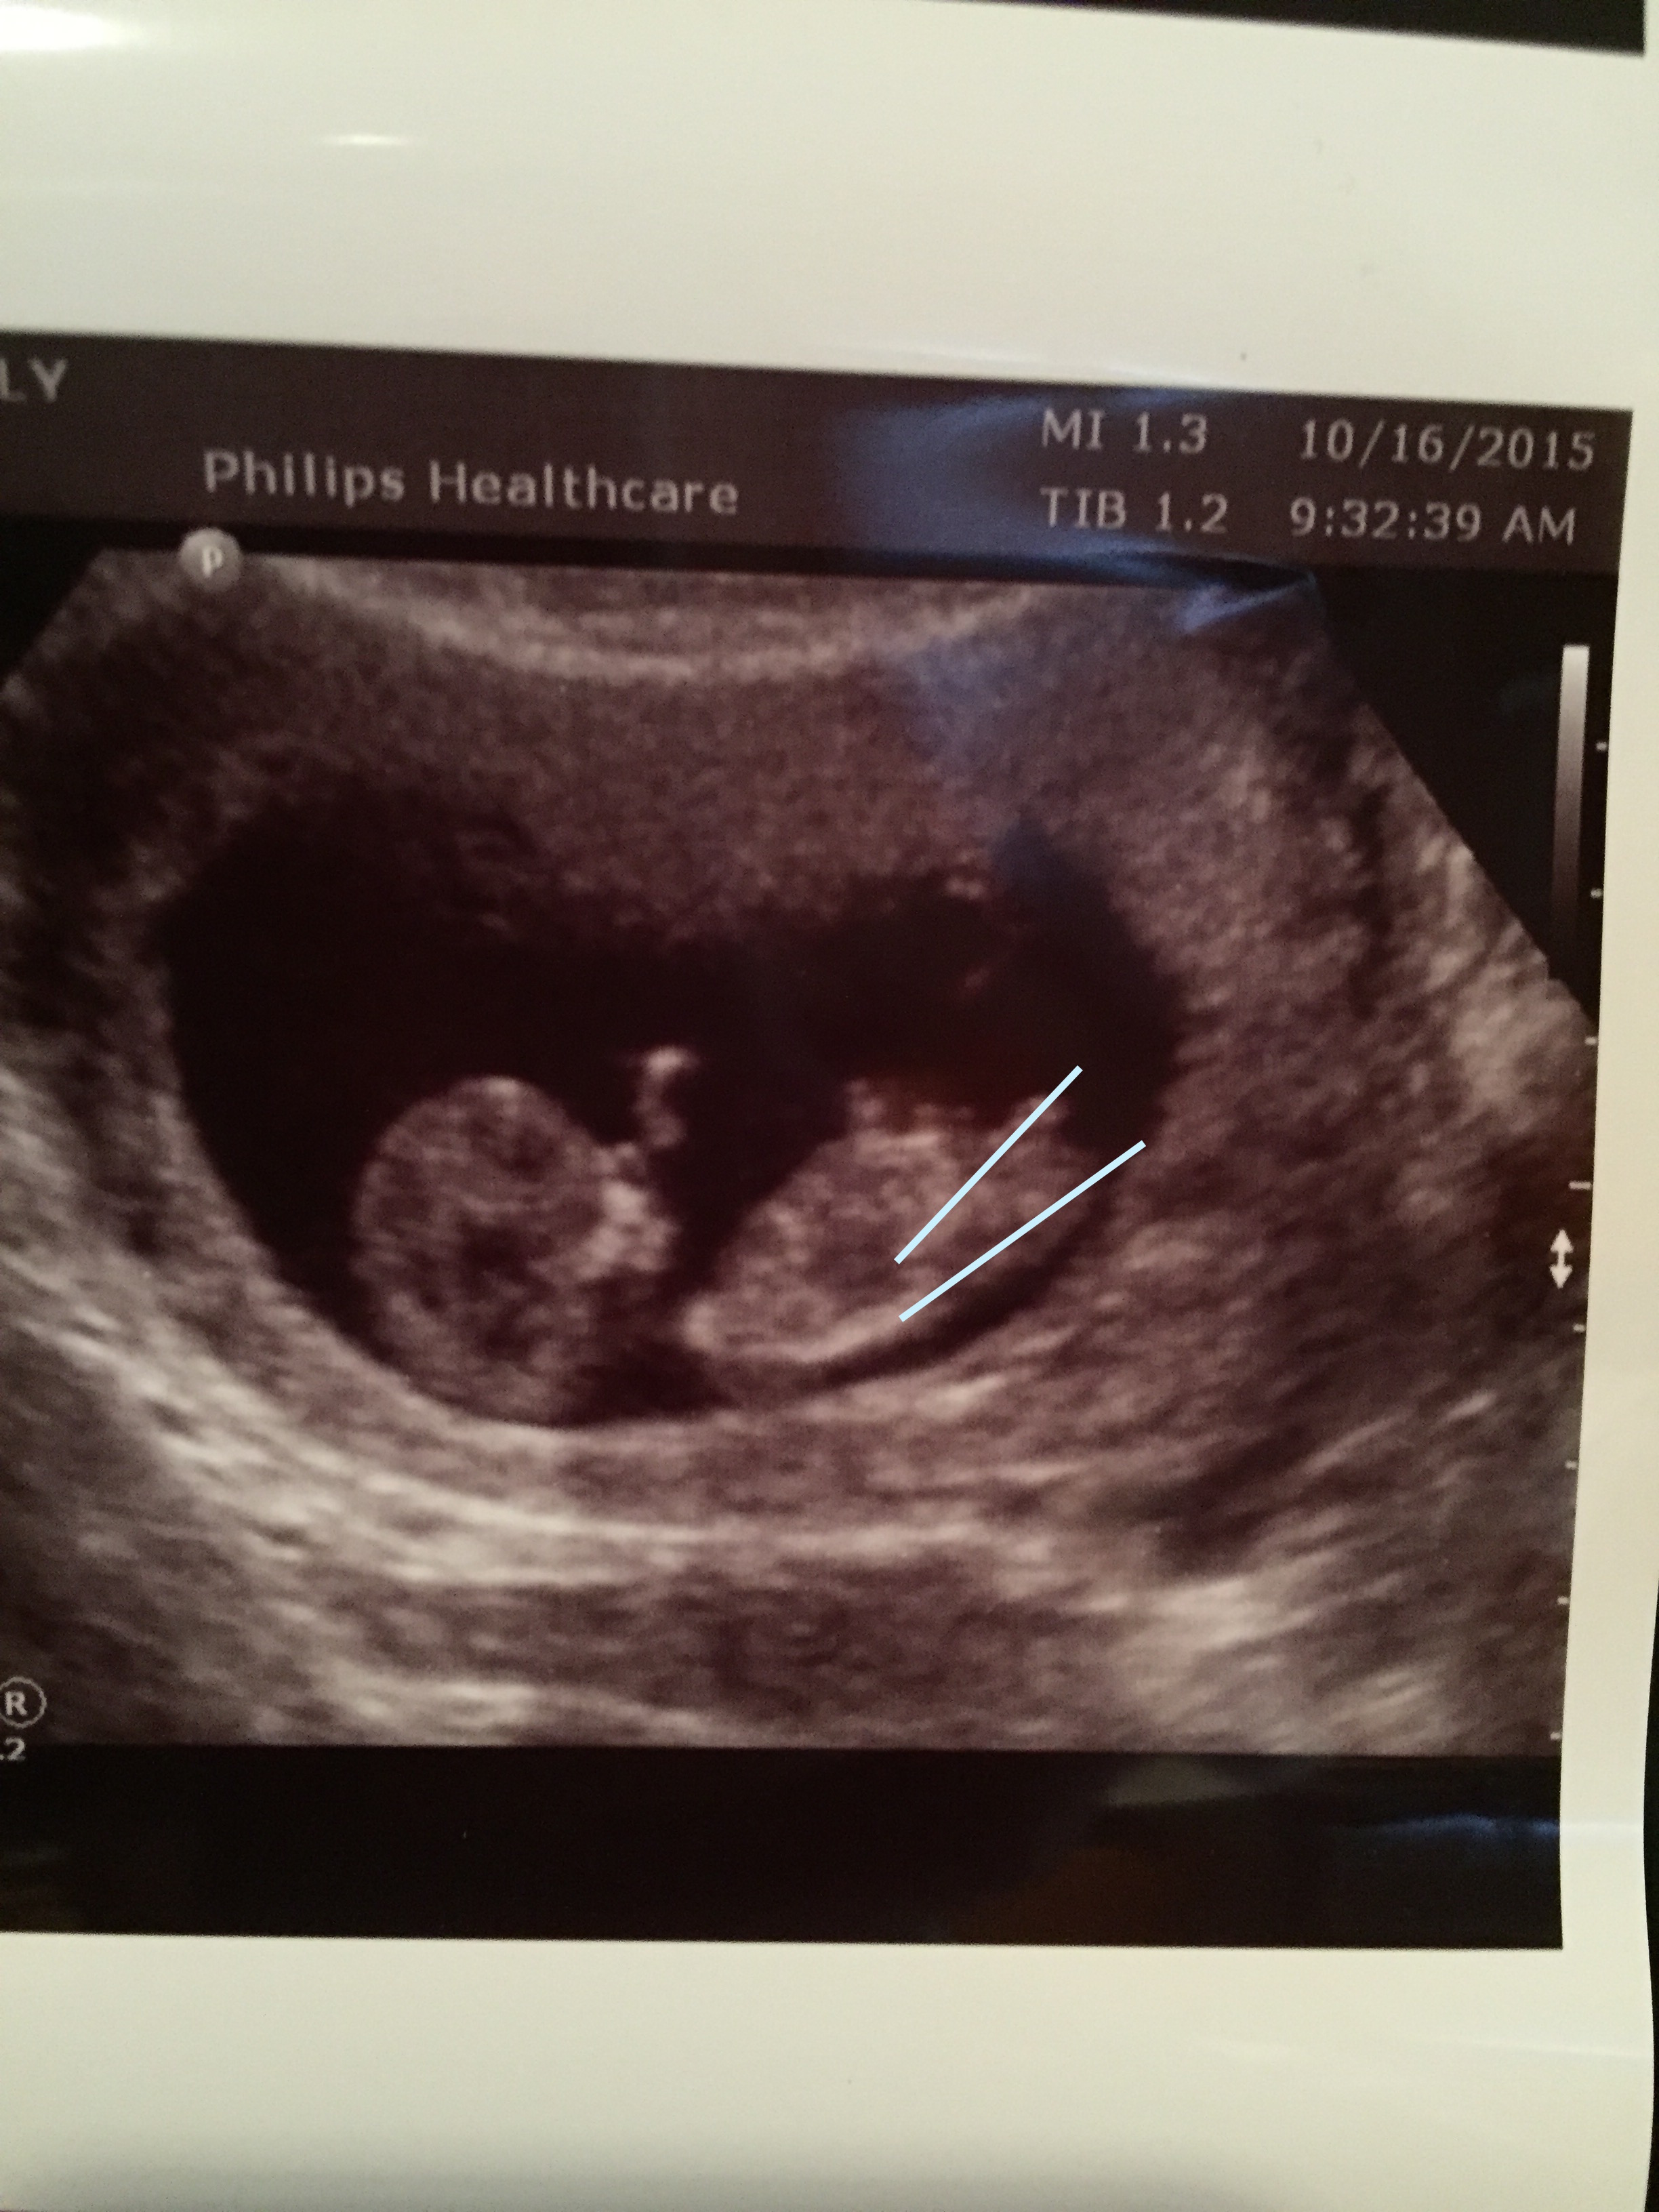

Attachment 28376Someone told me this is a boy nub. I previously posted two pics on here and got all boy guesses from other photos but someone said by looking at this picture from my sonogram( I didn't post this picture since I didn't feel like I could see anything) that the circle area is a boy nub. Any insight would be appreciated.Gender scan is on friday so any last guesses? Thanks so much ladies!!!Attachment 28374